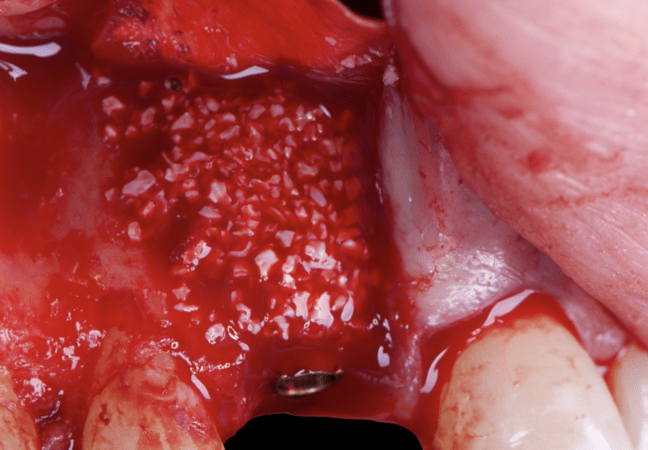

Given the significant buccal defect, guided bone regeneration (GBR) was performed simultaneously. A mixture of autologous bone and creos™ xenogain™ was applied to the defect and covered with a resorbable creos™ membrane to restore ridge width and support the buccal contour. In addition, a connective tissue graft was harvested and placed in the vestibular region to increase the thickness of keratinized mucosa. This combined approach addressed both hard and soft tissue deficiencies, providing the biological foundation for a stable and esthetic outcome.